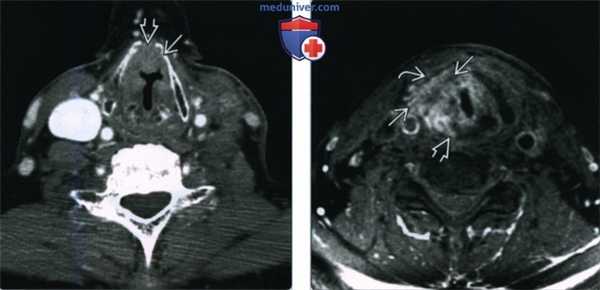

(Слева) При аксиальной КТ с КУ визуализируется небольшое вторичное внутреннее ларингоцеле в краниальных отделах окологортанного пространства слева.

(Справа) При аксиальной КТ с КУ на уровне голосовых связок визуализируется инфильтративное объемное образование (ПКР) левой голосовой связки, накапливающее контраст. При эндоскопическом исследовании было обнаружено распространение опухоли на ложную голосовую складку, лежащую выше. При КТ были выявлены признаки местного объемного воздействия, обусловленного вторичным внутренним ларингоцеле.